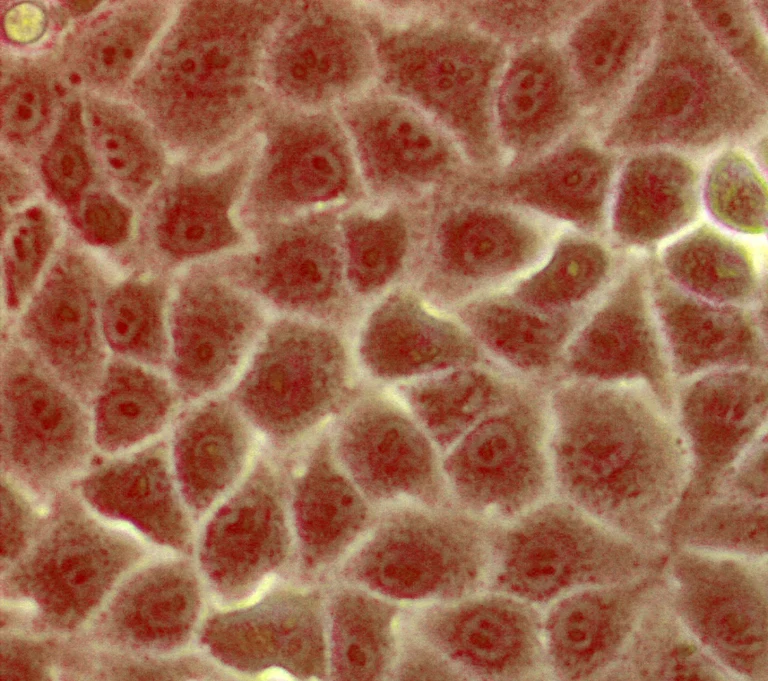

Nierenepithelzellen

von der Zwergfledermaus (Pipistrellus pipistrellus). Die Wissenschaftler zeigten an diesen Zellen, dass auch das Fledermaus-DPP4 als Rezeptor für das HCoV-EMC/2012 funktioniert. Rot ist der Zellkern mit der DNA zu erkennen, weiß sind die Zellgrenzen.